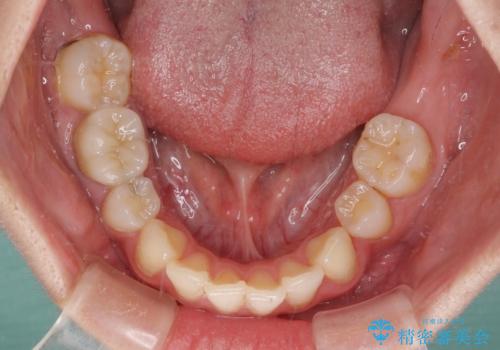

部分矯正を併用した奥歯のインプラント治療

- 左下欠損部のインプラント治療と、右下の歯の痛みを気にして来院された患者様です。

ただし、長期間欠損を放置していたことで、咬み合う上の奥歯が動いてしまっていたので、まずは上顎奥歯の部分矯正を行い、より理想的な咬み合わせを目指すこととしました。

まず生活歯髄療法を行い、その後部分矯正やインプラント処置を行いましたが、最初の処置から1年以上経っても右下奥の処置歯の神経組織に異常は認められませんでした。

部分矯正を行ったことで、違和感のない咬み合わせを達成することができました。